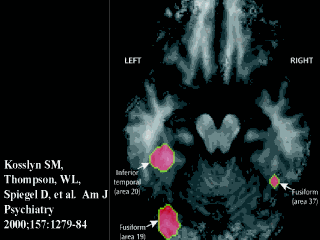

| Let me walk you through this. About 10 percent of people are highly hypnotizable. They took eight such individuals and showed them identical patterns in color or in grayscale while they were undergoing positron emission tomography of the brain -- PET scanning -- which looks at functional changes in the brain, in this case, local changes in blood flow. |